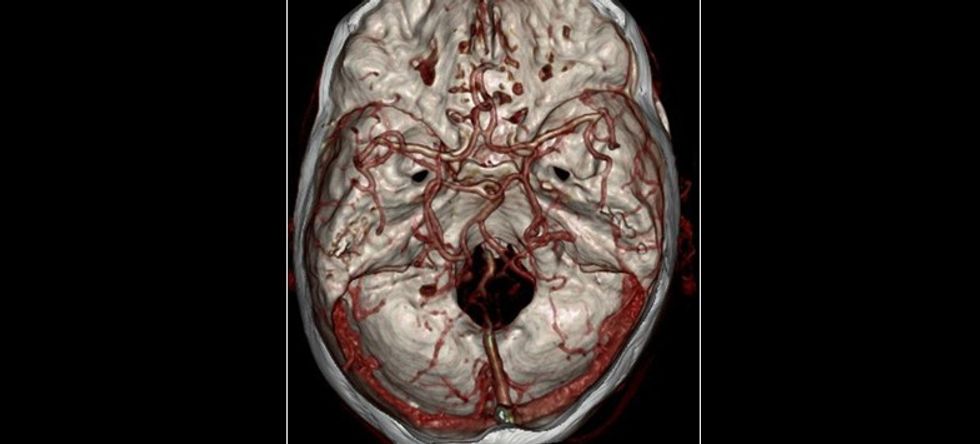

Imazhe të enëve të gjakut të trurit me tomografi të kompjuterizuar

TK përdoret për imazhimin e kokës, qafës, eshtrave, kurrizit, gjoksit, barkut, komblikut. Aparatet e reja shumë shtresore prej më së paku 6 shtresa me aplikim të kontrastit në enë të gjakut mund të bëjnë edhe angiografinë me TK të tërë trupit përveç të zemrës derisa ato prej 64 shtresa edhe koronarografinë me TK.

Imazhi i përfituar me TK jep edhe dimensionin e tretë që është thellësia.

Përparësitë: TK është procedurë e shpejtë, pa dhimbje dhe jo invazive. Me TK imazhet e përfituara janë mjaft të detajizuara dhe me mundësi të përpunimit të mëtutjeshëm edhe tredimensional të cilat mund të barten në film, CD ose edhe të shtypen në letër me ose pa ngjyra.